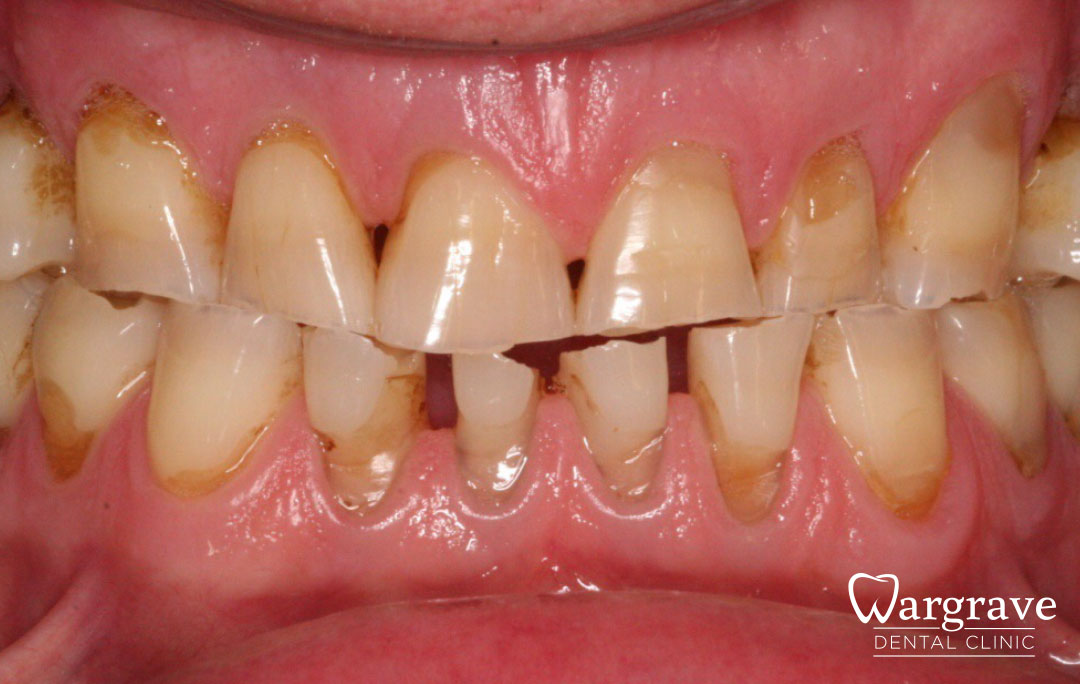

Healthy Smiles These are more advanced examples of different treatments available.All cases shown were carried out by Dr R Khurana unless otherwise stated. Immediate implants Anterior Mandible Bone Regeneration Anterior Mandibular Implant Bridge Maxillary Anterior Implant Bridge Implant stabilised ‘Life Like’ replacement dentures Implant Bridge after 10-years with zero bone loss Implant examples including ZBLC concepts Adhesive Bridge solution for a missing premolar Multidisciplinary care Orthodontics, Replacement veneers and composite bonding Adhesive Bridge solution for missing central incisors Replacement crown, Veneer and Composite Bonding Replacement Crowns and Veneer Injection Moulding using Composite Resin Equilibration Tooth Whitening to treat Developmental Discolouration